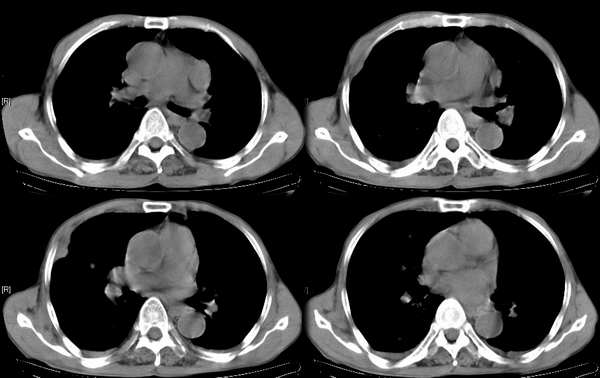

男,74岁,甲状腺肿30余年。现右颈部出现新肿块,疼痛,感乏力。

右颈部巨大软组织肿块影,范围较广,上至下颌角,下至颈静脉切迹。其最大层面位于右侧甲状腺区。肿块密度不均,其中有坏死液化区和班片状钙影,增强扫描见肿块实质区有强化。邻近结构挤压移位,部分结构侵蚀破坏,右侧多个颈深淋巴结肿大。两肺弥漫分布小结节影,以胸膜下为主,其大小不等,边缘光整。右侧胸壁亦见软组织结节影,纵隔多个淋巴结肿大及两侧锁骨上淋巴结肿大。

意见:右侧甲状腺癌并两肺、胸壁、纵隔淋巴结、颈深淋巴结、锁骨上淋巴结等广泛转移。